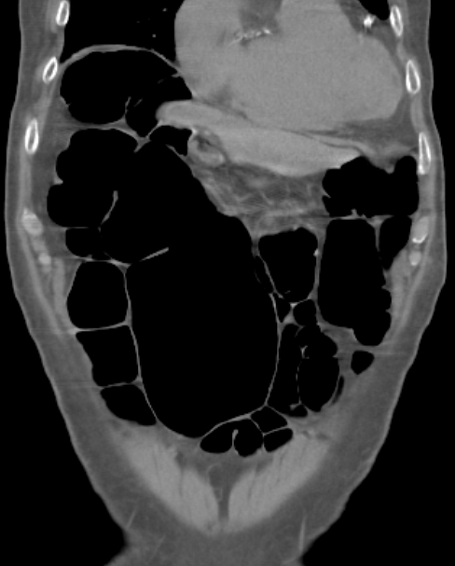

S状結腸軸捻転症

S状結腸軸捻転症とは、何らかの要因によって腸間膜を中心にS状結腸が捻じれている状態を指します。

• CT検査